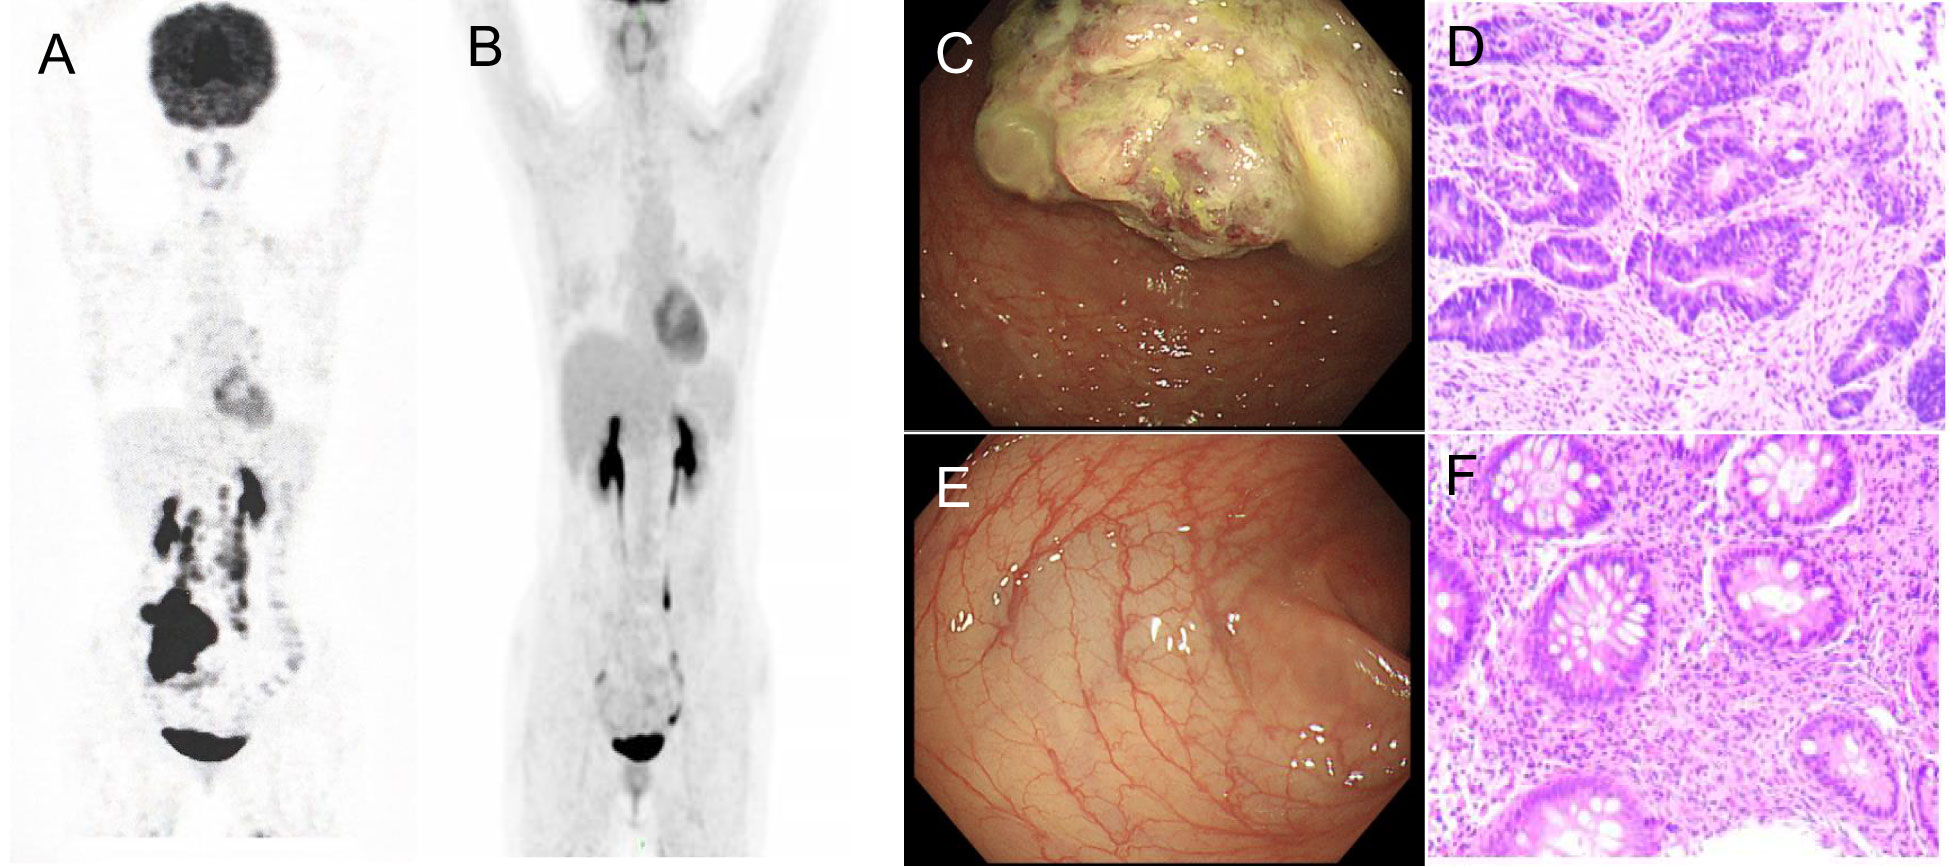

A 35-year-old female complaining of abdominal discomfort and diarrhea for several months was referred to a local hospital. Abdominal computed tomography (CT) revealed a neoplasm located in the right colon, and positron emission tomography/computed tomography (PET/CT) showed a thickened nodule in the retroperitoneal area (Figure 1A). There was no significant family history of colorectal cancer or extraintestinal malignancies related to Lynch syndrome. This patient was admitted to our hospital for further treatment.

Figure 1 PET/CT and coloscopy findings at baseline and after treatment. PET/CT showed disease status (A) before treatment and (B) after treatment. (C) The coloscopy showed the tumor in the right colon. (D) Immunohistochemistry of pre-treatment biopsy confirmed tumor cells. (E) Post-treatment coloscopy did not display any neoplasm. (F) Pathologic analysis of the tissue manifested chronic mucositis.

Coloscopy was performed, and pathological analysis of the tumor revealed adenocarcinoma (Figures 1C, D). Immunohistochemistry showed positivity for MLH1, MSH2, and MSH6 and negativity for PMS2. Next-generation sequencing confirmed that the tumor was MSH-H. However, the patient refused immunotherapy. Thus, a first cycle of chemotherapy consisting of mFOLFOX6 plus bevacizumab was administered on 1 October 2021. After three cycles, an abdominal CT scan showed an impressive reduction in tumor size in the right colon, while the retroperitoneal lesion remained stable. A chest CT revealed interstitial pneumonia (Figure 2), but the patient did not experience dyspnea. A multidisciplinary team (MDT) discussion, including surgical staff, was organized to formulate further treatment plans. Specialists recommended pembrolizumab, nivolumab, or nivolumab in combination with ipilimumab—all approved therapies for patients with metastatic MSI-H/dMMR colon cancer regardless of their eligibility for intensive therapy. Since the patient could not afford the expenses of the recommended courses of treatment, envafolimab was suggested instead. With patient and treatment teams reaching an agreement, the patient was started on envafolimab (150 mg, administered subcutaneously, once weekly) on 21 September 2021. Interstitial pneumonia did not worsen over the course of treatment, as evidenced by chest CTs. One month later, the patient experienced pain in her extremities with elevated creatine kinase (CK) and creatine kinase isoenzyme MB (CK-MB) levels. No significant laboratory findings involving cardiac troponins or N-terminal pro-brain natriuretic peptide were observed. We consulted cardiologists in our hospital. who excluded the possibility of ICI-related myocarditis but suspected myositis. However, she refused a proposal of muscle biopsy. According to the Management of Immune Checkpoint Inhibitor-Related Toxicity section of the Guidelines of the Chinese Society of Clinical Oncology, the symptom is classified in Grade 1, for which dose reduction or discontinuation are not considered. Therefore, nonsteroidal anti-inflammatory drugs (NSAIDs) and low-dose methylprednisolone (12 mg daily) were administered, and immunotherapy was continued. Decreased CK and CK-MB were observed three days after management (Figure 3). On 1 March 2022, a CT scan showed a decrease in volume, prompting a second MDT to suggest the patient continue treatment. A greater reduction in lesion size was observed during a follow-up CT scan in May 2022. Moreover, envafolimab with methylprednisolone (4 mg, daily) was well tolerated. Thirty-six cycles later, the lesion in the right colon disappeared on an abdominal CT scan performed on 18 August 2022 (Figure 4). Post-treatment colonoscopy revealed no neoplasm, and immunohistochemistry revealed chronic mucositis (Figures 1E, F). PET/CT also showed that the patient achieved CR efficacy (Figure 1B). Given the safety of envafolimab, the patient was started on 400 mg of envafolimab every 3 weeks without additional adverse events. CK and CK-MB levels remained low.